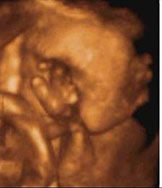

四维彩超能多方位、多角度、立体显示胎儿生长发育情况,为早期诊断胎儿先天性体表畸形如唇裂,脊柱裂,大脑、肾、心脏、骨骼发育不良等,和先天性心脏疾病提供全面的科学依据。

怎样选择排畸时间?| 仪器 | 美国E8四维 | 普通四维 |

| 画质 | 立体动态成像,画质比较清晰 | 动态成像画质普通 |

| 优势 | 多方位、角度地观察孕宝宝的生长发育,对孕妇潜藏的疾病进行检测,无辐射。 | 较准确地动态呈现腹中胎儿的生长发育情况 |